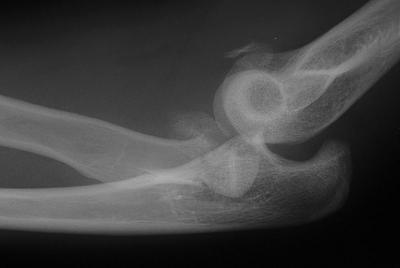

Redisplaced 2 days later: